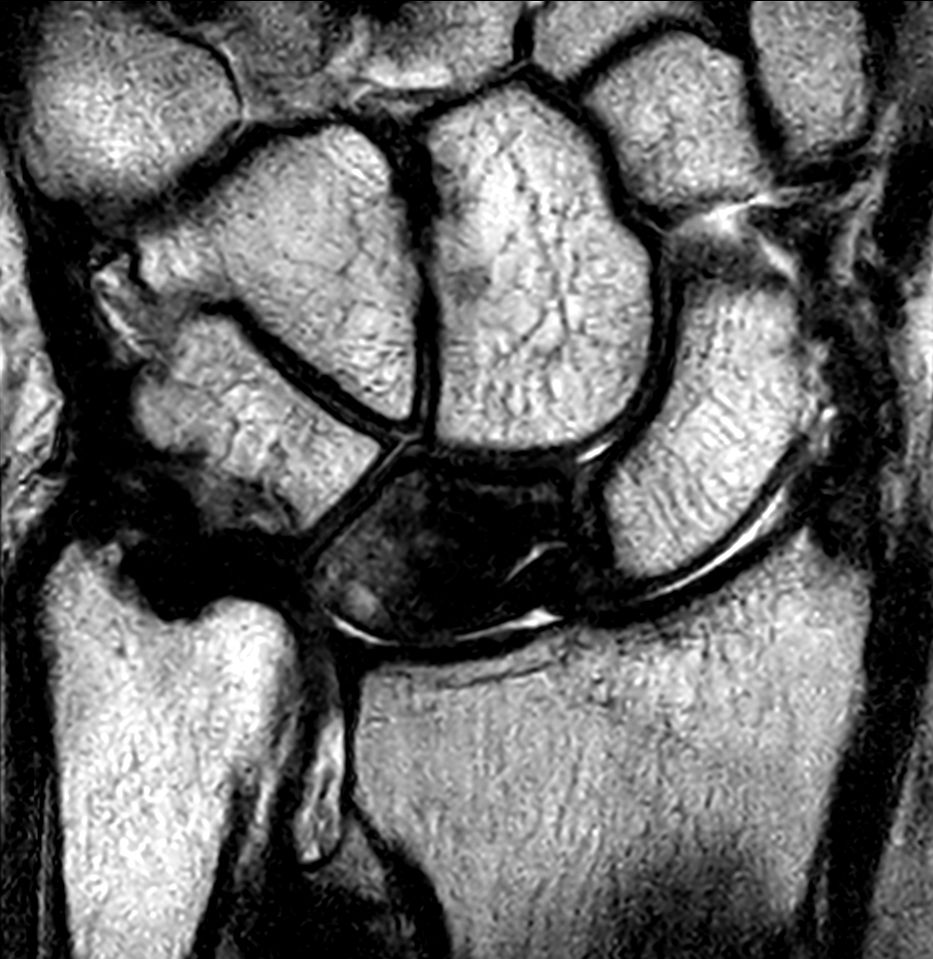

Patient with a lesion in his wrist. dS Microscopy coil set is used, consisting of two 47 mm coils, for small field-of-view imaging with high in-slice spatial resolution and a high signal-to-noise ratio. Compressed SENSE is used in all sequences to shorten the overall exam time for the patient.

Coronal 3D T2w TSECompressed SENSE